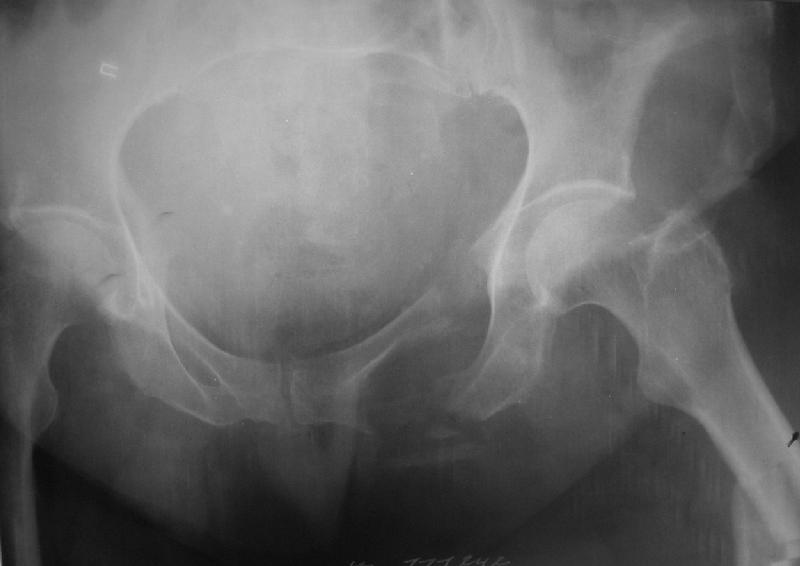

Здравствуйте уважаемые коллеги! Поступила пациентка, 61г, через 1 месяц после травмы, с двусторонним ротационно-нестабильным повреждением тазового кольца: перелом боковых масс крестца с обеих сторон, переломы лонной и седалищной костей слева, отрывные переломы передних остей левой подвздошной кости, сегментарный перелом левой подвздошной кости. Кроме того у пациентки имеется сегментарный перелом левого бедра. Перелом бедра не вызывает вопросов - планируем блокируемый остеосинтез стержнем, а вот при обсуждении тактики лечения переломов костей таза возник вопрос о необходимости синтеза остей подвздошной кости, учитывая сроки с момента травмы и наличие остеопороза могут возникнуть технические сложности. Если у кого-нибудь собственный опыт или ссылки на литературу об отдаленных результатах при не восстановлении сгибательного аппарата бедра?

По поводу перелома боковых масс крестца с двух сторн, мне кажется справа нет повреждения. надо однозначно синтезировать таз, при наличии ЭОПа можно синтезировать лоннуую ксоть одним длдинным винтом, крестец можно так же 2 мя винтами. Перелом крыла подвздошной кости, можно синтезировать на пластинке или так же винтами. Пусть не смущают сроки перелома, синтезировать можно. По поводу перелома бедра, согласен, нужен блокирующий синтез. Вот возникает вопрос. Отсинтезировать бедро, чтоб потом оно не было опорным из-за неадекватной стабилизации таза? Зачам тогда синтезировать?

Уважаемые коллеги, в продолжение обсуждения перелома костей таза с отрывами остей досылаю R-снимки (КТ и КТ с 3d реконструкцией)